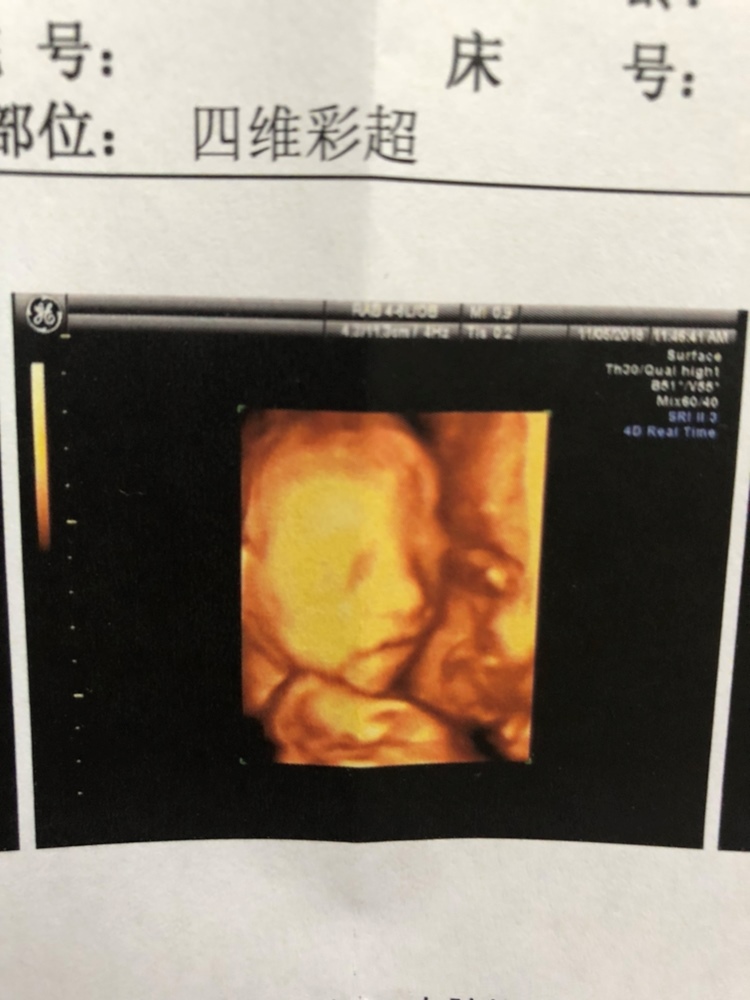

孕26周+4天